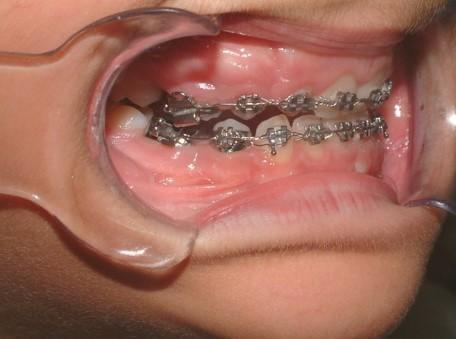

Γ4. Ελεγχος ανατολής κυνοδόντων και διάνοιξη υπερώας (ref.15,16)

Στα 7 χρόνια του παιδιού εξετάζουμε με πανοραμική ακτινογραφία τη θέση των μονίμων άνω κυνοδόντων στο οστό και αναλόγως πράττουμε.

Αν δεν υπάρχει αρκετός χώρος για αυτά,κάνουμε διεύρυνση της υπερώας με ορθοπεδικό μηχάνημα.

024 Με

τον τρόπο αυτό τα βοηθάμε